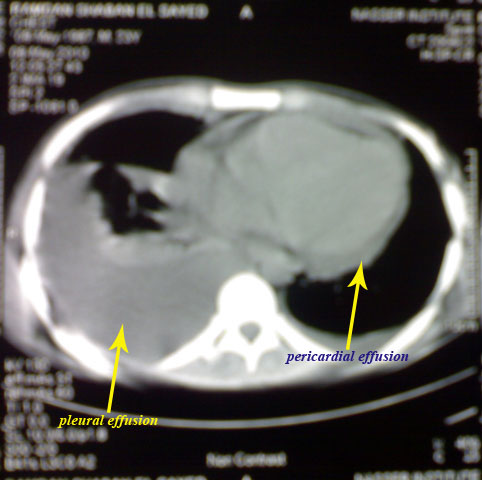

He sought medical advice that revealed bilateral pleural effusion,

then he was admitted in the chest department where both bilateral

pleural aspirates and biopsy studies revealed nothing "non-specific

pleurisy".

Now he presented feverish with facial flushing, oro-genital ulcers,

polyarthritis, lymphadenopathy, bilateral pleural and pericardial

effusion and ascites.